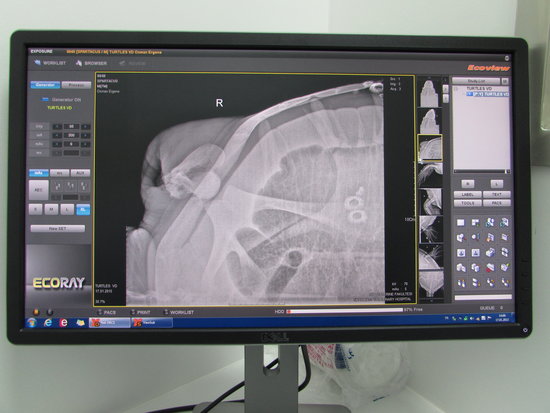

Dev Yeşil Kaplumbağa’ya Ultrasonografi Ve Endoskopi Uygulandı

İlk gün geldiği duruma göre iyi anlamda gelişmeler gösteren yeşil kaplumbağanın kan değerleri yapılan laboratuvar testleri sonucunda ciddiyetini korumaktadır. Kendi isteği ile beslenme hareketleri başlamamasından dolayı sıvı tedavisi ve gastrik sonda ile beslenme devam etmektedir. Çekilen röntgen sonucunda kopan yüzgecinin bölgesinde eski bir kırık tespit edilmiştir ve yüzgecin kırığa bağlı koptuğu düşünülmektedir. Yapılan ultrasonografi ve endoskopi sonucunda iç organlarda ve yemek borusunda herhangi bir patolojiye rastlanmamıştır. Doğal ortamı, su ısı seviyesi ve su tuz oranı dengelenen yeşil kaplumbağanın hareketliliği artmış ve çevreye ve olaylara tepkisi başlamıştır.